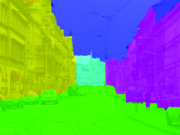

Given an input image, , the goal of a typical image segmentation system is to assign every pixel in a specific label where each label represents a structure of interest. Several traditional segmentation algorithms have been proposed for assigning labels to pixels; these include thresholding (Otsu, 1975; Sahoo et al., 1988), region-growing (Adams and Bischof, 1994; Pohle and Toennies, 2001; Pan and Lu, 2007), watershed (Vincent and Soille, 1991; Grau et al., 2004; Hamarneh and Li, 2009) and optimization-based methods (Grady, 2012; McIntosh and Hamarneh, 2013a; Ulén et al., 2013). The existence of noise, low contrast and objects complexity in medical images, typically cause the aforementioned methods to fail. In addition, all these traditional methods assume that objects’ entire appearance have some notion of homogeneity; however, this is not necessarily the case for complex objects (e.g. multi-region cells with membrane, nucleus and nucleolus; or brain regions affected by magnetic field of a magnetic resonance imaging (MRI) device non-uniformity). Many real-world objects are better described by a combination of regions with distinct appearance models. This is where more elaborate prior information about the targeted objects becomes helpful.

In general, a segmentation problem can be formulated in a spatially discrete or continuous domain. In the community that advocates continuous methods, it is assumed that the world we live in is a continuous world (continuous ). However, images captured by digital cameras are discrete both in space and color/intensity. The discretization in space is called sampling (discrete ) and the discretization in color/intensity or value space is called quantization. Given this categorization, we have four different cases for image representation (Figure 1).